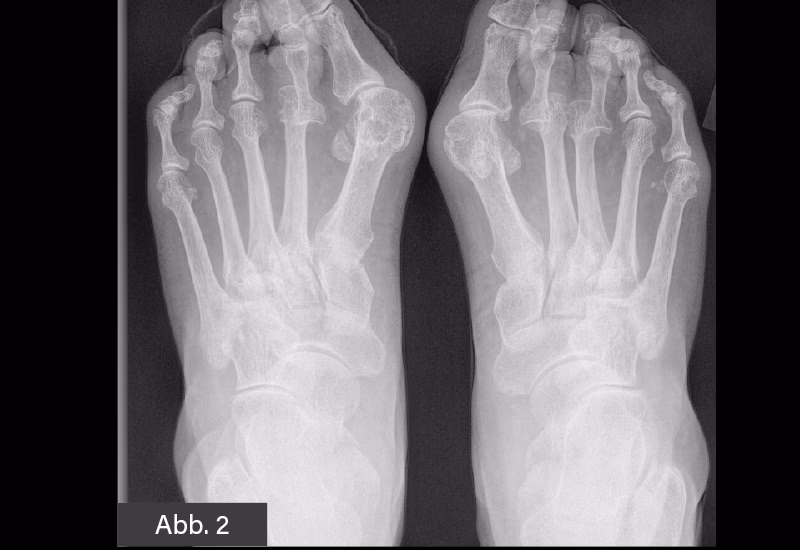

Hallux rigidus er en form for slidgigt (artrose), der specifikt rammer grundleddet i storetåen. Dette led, kaldet metatarsophalangealleddet (MTP-leddet), er afgørende for vores evne til at gå korrekt, da det bøjer ved hvert skridt, vi tager, især under afsættet. Ved slidgigt nedbrydes den glatte brusk, der dækker knogleenderne i leddet, gradvist. Uden denne beskyttende brusk begynder knoglerne at gnide mod hinanden, hvilket fører til smerte, inflammation og dannelse af knogleudvækster (osteofytter). Over tid fører denne proces til, at leddet bliver mere og mere stift, hvilket begrænser tåens bevægelighed markant. Tilstanden udvikler sig typisk langsomt over mange år og er den mest almindelige form for slidgigt i foden.

- Knogleudvækster (osteofytter): Der kan dannes en hård bule eller knyst oven på leddet. Disse knogleudvækster kan skabe tryk og ubehag i sko.